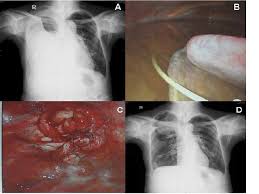

Role Of Medical Thoracoscopy In The Management Of Multiloculated Empyema Bmc Pulmonary Medicine Full Text

Role Of Medical Thoracoscopy In The Management Of Multiloculated Empyema Bmc Pulmonary Medicine Full Text from media.springernature.com

A pleural effusion is accumulation of excessive fluid in the pleural space, the potential space that surrounds each lung. Case contributed by dr prashant mudgal. Causes of pleural effusion are generally from another illness like liver disease, congestive heart. Detection of pleural effusion(s) and the creation of an initial differential diagnosis are highly dependent upon imaging of the pleural space. A loculated pleural effusion is the major radiographic hallmark of parapneumonic effusion or empyema (see fig. Pleural effusion with segmental and lobar opacities. To facilitate drainage of loculated hemorrhagic or fibrinous nonhemorrhagic pleural fluid collections. Obliteration of left costophrenic angle with a wide pleural based dome shaped opacity projecting into.

The precise pathophysiology of fluid accumulation varies according to underlying aetiologies. Pleural infection pleural inflammation pleural malignancy (most often pleural fluid analysis findings: In addition, a diagnostic and therapeutic thoracentesis of a l > r pleural effusion was performed. .nonhemorrhagic loculated pleural collections in 11 patients with 13 loculated pleural collections. If none is present the fluid is virtually always a transudate. Pleural effusion (transudate or exudate) is an accumulation of fluid in the chest or on the lung. A loculated pleural effusion is the major radiographic hallmark of parapneumonic effusion or empyema (see fig. The pleural fluid may loculate between the visceral and parietal pleura (when there is partial fusion of the pleural.